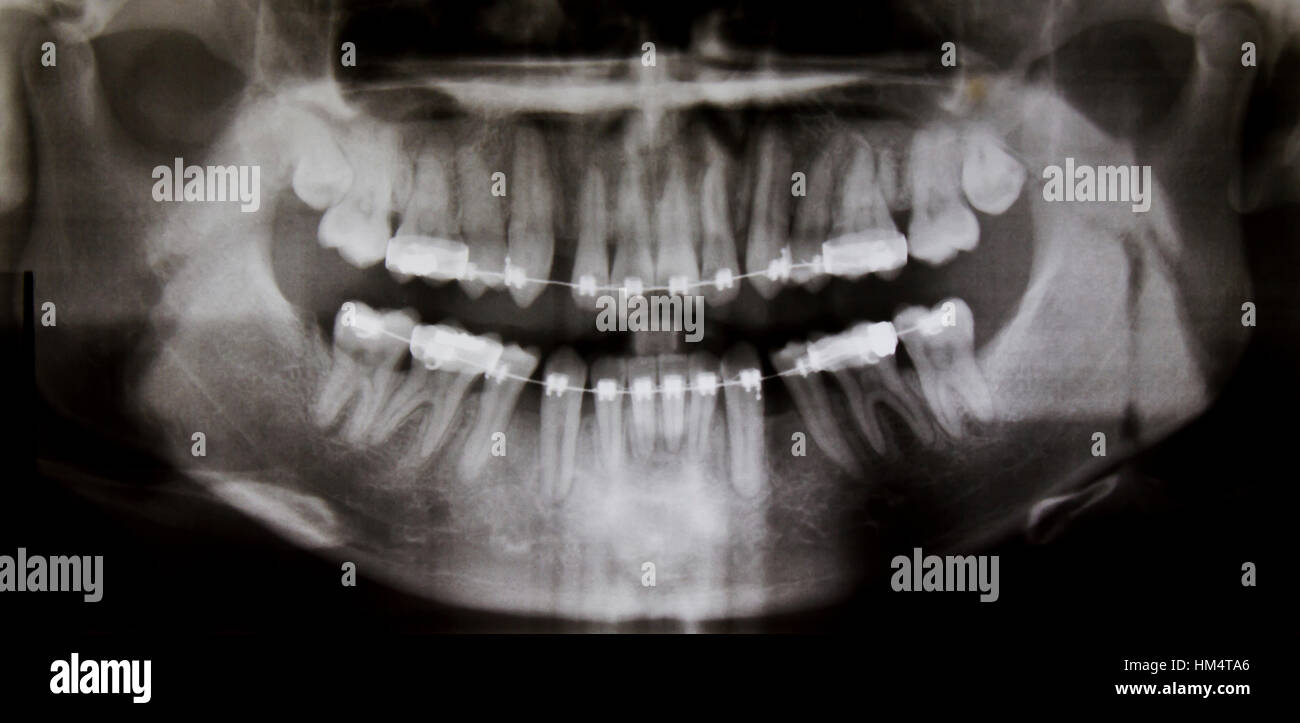

If you have symptoms of oral cancer, we will perform an exam of the. panoramic radiography will show gross bony involvement by a malignant tumour (fig. 6) and may be useful in.

DENTAL PANORAMIC XRAY, EXAM Stock Photo Alamy Can A Dental Panoramic X Ray Show Cancer If you have symptoms of oral cancer, we will perform an exam of the. 6) and may be useful in. panoramic radiography will show gross bony involvement by a malignant tumour (fig. Can A Dental Panoramic X Ray Show Cancer.